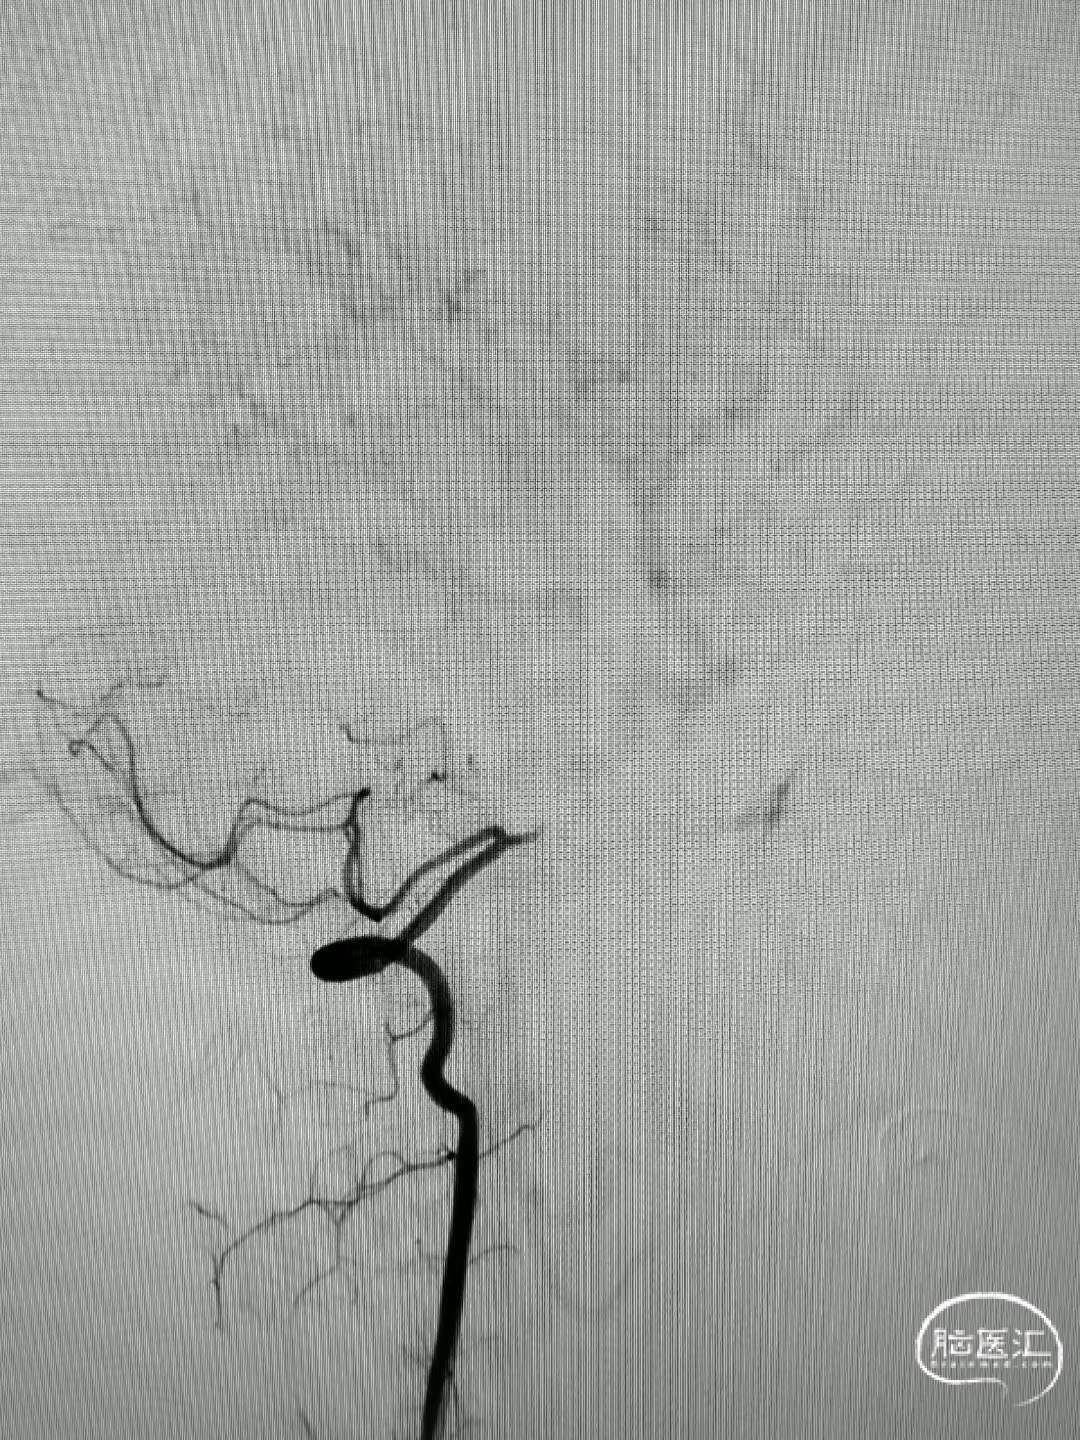

造影见基底动脉闭塞。

13a93e99538580fffabaee9f45c6786a.jpg